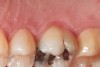

Figure 5   The red, irregular surface on the palatal surface of a maxillary molar can be an early sign of reflux.

Figure 5